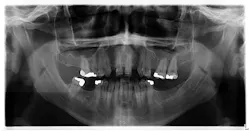

Upon initial assessment, the panoramic radiograph is insignificant (figure 3).

- Radiographic presentation is not typically immediately present; however, once the disease progresses and resorbs through the trabecular bone, it will manifest radiographically as a faint, blotchy, mottled lesion with indistinct margins.